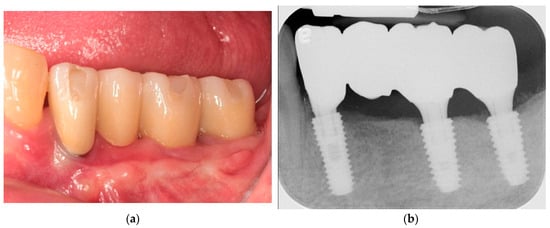

Utilization of Tenting Pole Abutments for the Reconstruction of Severely Resorbed Alveolar Bone: Technical Considerations and Case Series Reports

2. Case Presentations